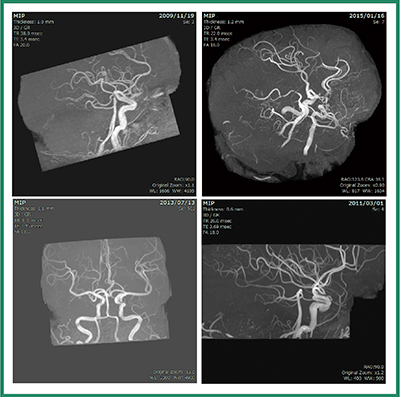

前述した各種解析アプリケーションの追加に加え,既存のアプリケーションに対し,MRI関連の機能拡張を行っている。3Dビューワに搭載している脳実質抽出に内頸動脈を含めた抽出を行う機能(図5),乳腺解析(図6),開頭シミュレータ/テンソル解析にMRI腫瘍の半自動抽出機能などを追加している。

図5 MRA自動抽出結果例

異なるメーカーのMRI装置においても,頭部MRA画像(4症例)に対しウイリス動脈輪を中心とした抽出を行うことができる。また,マクロ機能から1クリックで血管領域を含む抽出,MIPレンダリングの表示まで行うことができる。